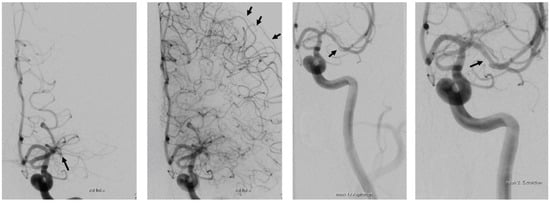

Case Report Continued